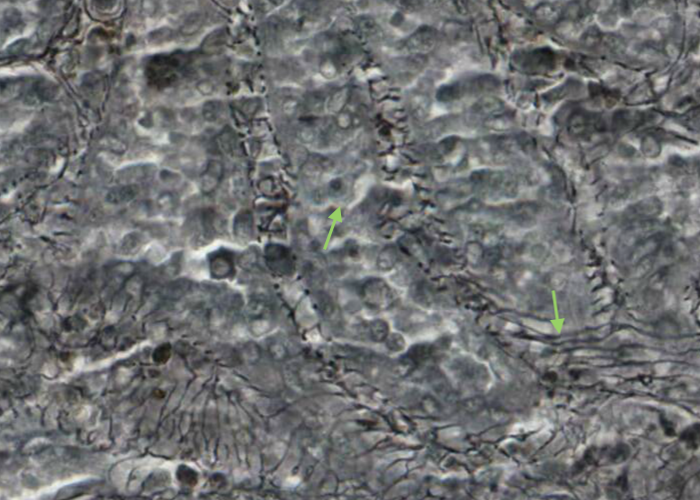

Each sinusoid is lined with specialized endothelial cells that are cigar shaped instead of flat. In cross section the endothelial cell nucleus looks round and bulges into the lumen of the sinusoid. Where the section misses the nucleus the cell looks like a tiny bleb at the edge of the sinusoid.

The endothelial cells do not form a continuous sheet - slits between them allow blood cells to percolate in and out.

In cross section the endothelial cell nuclei look round and bulge into the lumen of the sinusoid. The nuclei of the endothelial cells look elongate when sectioned longitudinally. The cells are held in place by reticular fibres wrapped circumferentially around the outside of the sinusoid.

You will recall that the internal organization of reticular tissues are reflected in, and were programmed to be where they are, by the reticular cells anchored to reticular fibres. Snoop around at those fibers surrounding each sinusoid, and in the splenic cords, white pulp and central arteries. Pretty neat, eh, especially the parallel fibers banding around the sinusoid.